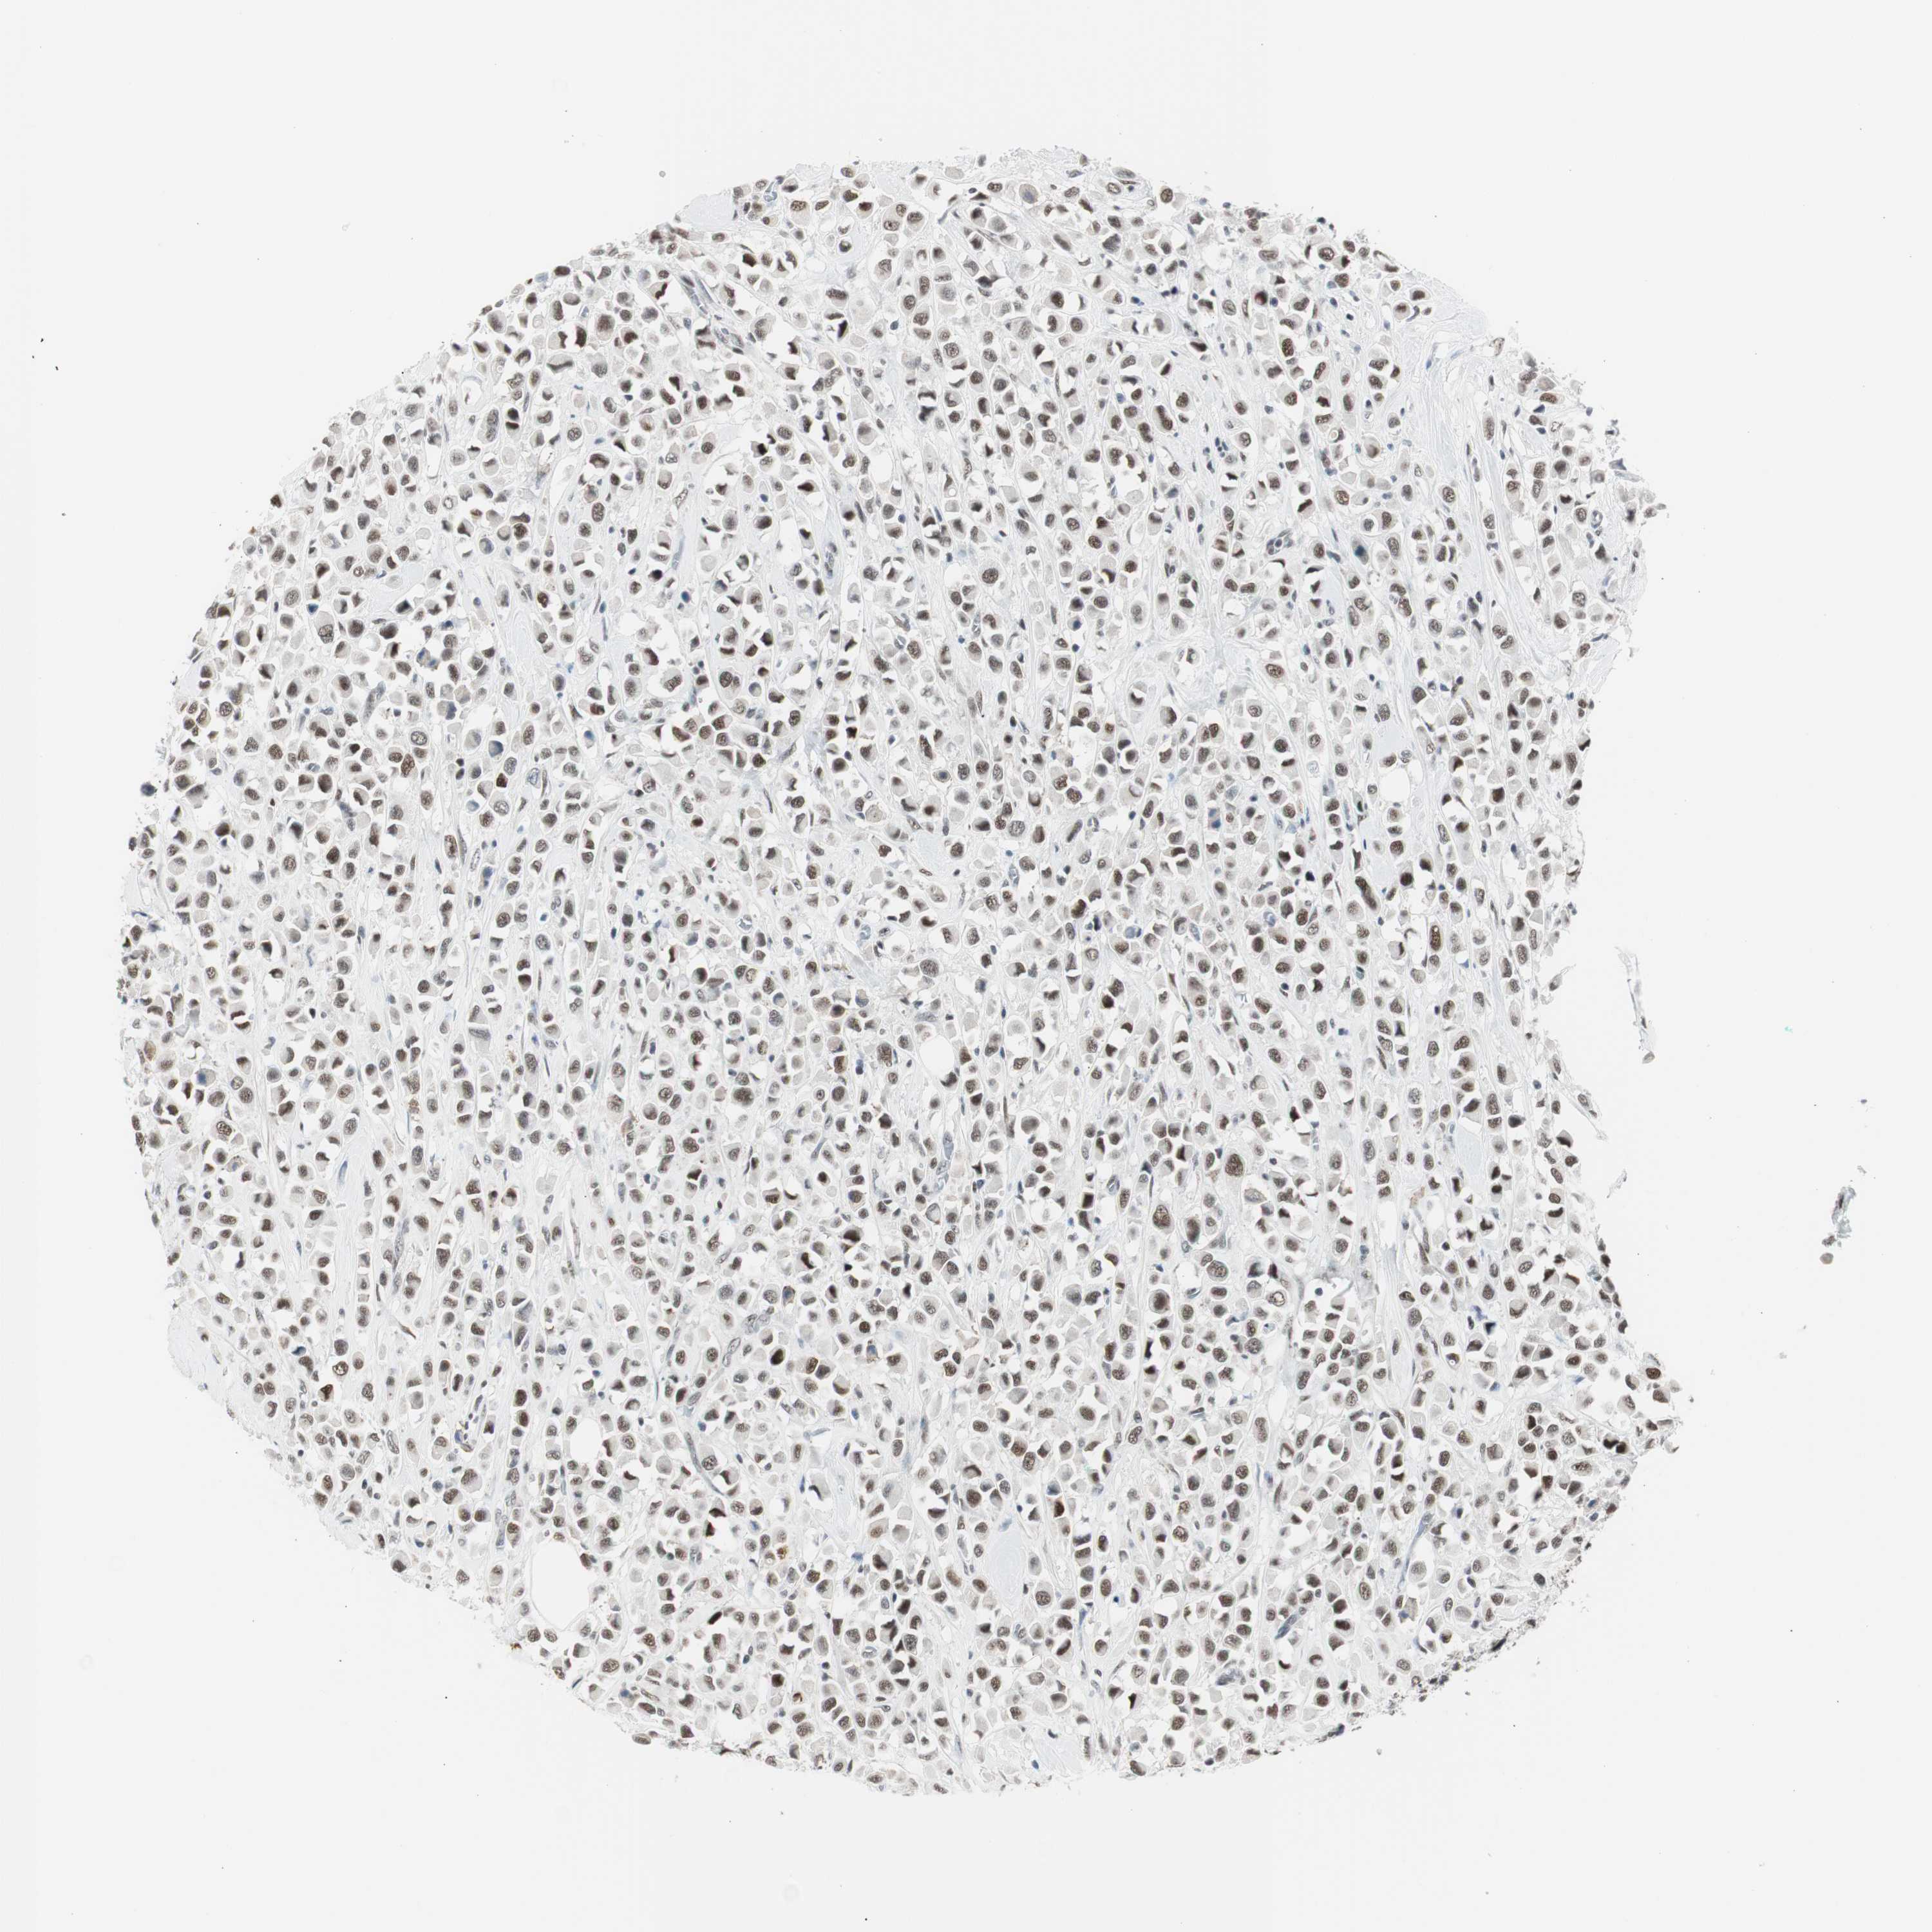

CANCER BREAST CANCER Show tissue menu

BRCA TCGA BRCA VALIDATION PROTEIN EXPRESSION